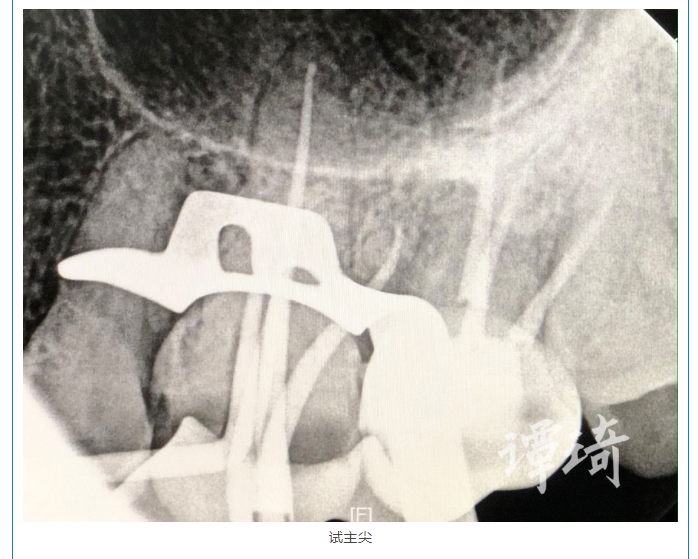

顯微治療病例之45 | 譚琦:左上后牙根管治療一例